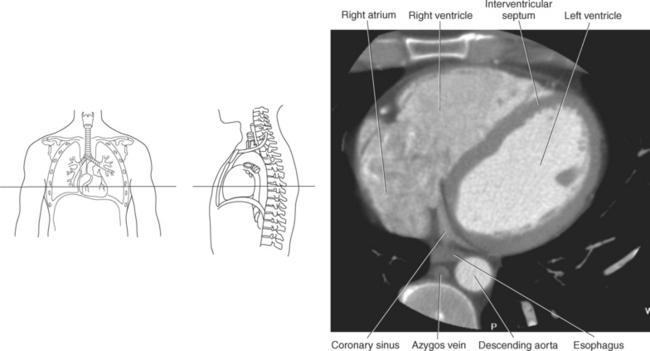

The heart is a hollow, four-chambered muscular organ located within the middle mediastinum. It is approximately the size of a large clenched fist and is situated obliquely in the chest with one third of its mass lying to the right of the median plane and two thirds to the left. The heart can be described as being roughly trapezoid shaped (Figure 6.33). The superficial relationships of the heart include the base, apex, three surfaces (sternocostal, diaphragmatic, pulmonary), and four borders (right, inferior, left, and superior). The broad base (posterior aspect) is the most superior and posterior portion of the heart. It is formed by both atria, primarily the left atrium, and gives rise to the great vessels. The apex is formed by the left ventricle and points inferiorly, anteriorly, and to the left. It is located at the level of the fifth intercostal space, just medial to the midclavicular line. The sternocostal (anterior surface) is formed primarily by the right atrium and right ventricle with a small contribution from the left ventricle. The diaphragmatic (inferior surface) rests on the central tendon of the diaphragm and is formed by both ventricles and a small portion of the right atrium. The pulmonary (left surface) is formed mainly by the left ventricle and fills the cardiac notch of the left lung. The borders of the heart represent the external surfaces of the cardiovascular silhouette in radiographic profile. The borders include the right border, formed by the right atrium and located between the superior and inferior venae cavae; the left border, formed by the apex of the heart or the left ventricle; the superior border, formed by the right and left atria; and the inferior border, which is formed primarily by the right ventricle with a small contribution from the left ventricle (Figures 6.33 through 6.35).

The walls of the heart consist of three layers: (1) epicardium, the thin outer layer that is in contact with the pericardium; (2) myocardium, the thick middle layer consisting of strong cardiac muscle; and (3) endocardium, the thin, endothelial layer lining the inner surface. The endothelial layer also lines the valves of the heart and is continuous with the inner lining of the blood vessels. The heart is divided into four chambers: the right and left atria and the right and left ventricles. The two superior collecting chambers called atria are divided by the interatrial septum. During embryonic development an oval opening exists within the interatrial septum called the foramen ovale. This opening allows blood flow between the right and left atria during fetal lung development. At birth, the foramen ovale closes, leaving a small depression in the septal wall called the fossa ovalis in the adult heart. The two inferior pumping chambers called ventricles are divided by the interventricular septum (Figure 6.39).

The right atrium forms the right border of the heart and receives deoxygenated blood from the body via the superior and inferior venae cavae and from the coronary sinus and cardiac veins that drain the myocardium. A small muscular embryonic appendage, the right auricle, projects upward and toward the left from the right atrium, covering the root of the aorta (Figure 6.40). The right ventricle lies on the diaphragm and comprises the largest portion of the anterior surface of the heart. It receives deoxygenated blood from the right atrium and forces it into the pulmonary trunk for conveyance to the lungs. Projecting off the inferior surface of the ventricular walls are conical-shaped projections of cardiac muscle called papillary muscles that anchor the cusps of the tricuspid valve to the right ventricle (Figure 6.39). The left atrium lies posterior to the right atrium and is the most posterior surface of the heart. It also has an embryonic appendage, the left auricle, that projects to the left of the pulmonary trunk over the superior surface of the heart. The left atrium receives oxygenated blood directly from the lungs via the four pulmonary veins (two on each side). The left ventricle forms the apex, left border, and most of the inferior surface of the heart. It receives oxygenated blood from the left atrium and pumps it into the aorta for distribution throughout the systemic circuit. The myocardium of the left ventricle is normally three times thicker than that of the right ventricle, reflecting the force necessary to pump blood to the distant sites of the systemic circulation (Figures 6.41 through 6.52). Two papillary muscles project from the ventricular walls to anchor the bicuspid valve to the ventricle (Figures 6.39 and 6.47).